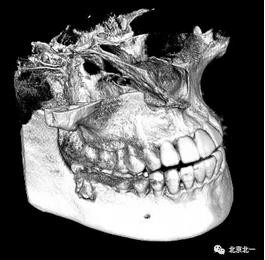

圖四:三維重建

圖五:三維重建可見牙冠突破舌側(cè)